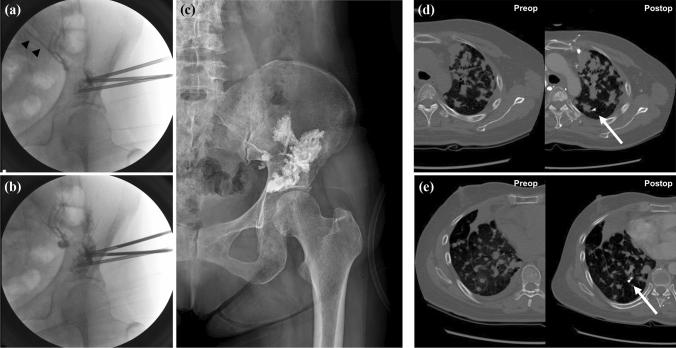

In advanced cancer patients, pelvic bone metastasis often causes pain and gait disturbance. The use of percutaneous bone cement [polymethylmethacrylate (PMMA)] injection for pain management and strengthening in pelvic bone metastasis has rarely been reported. To evaluate this method, we aimed to determine surgical outcomes and complications over a long-term follow-up period using a large patient group.

We retrospectively collected data from 178 patients who underwent percutaneous cementoplasty for pelvic metastatic lesions, 201 in total. Surgical outcomes evaluated included pain reduction and improvement of ambulation. Mortality within 1 month after procedure and pulmonary embolism caused by thrombus, fat, tumor emboli, or bone cement were investigated as surgical complications. For long-term survivors, pain relapse and mechanical failure were analyzed. The mean follow-up period was 12.6 months, and there were 159 fatalities at last follow-up.

The mean regional pain numerical rating scale scores decreased from 6.1 preoperatively to 2.4 1 month after procedure (p < 0.01). Gait function was maintained, worsened, and uncheckable in 68%, 24%, and 8% of patients, respectively, 1 month after procedure. Of long-term survivors followed up for > 12 months (n = 53), there were no significant changes in serial plain radiographs, and regional pain aggravation was observed in 9%. Pulmonary cement embolism and bone cement implantation syndrome was observed in 11% and 10%, respectively. However, all patients with these complications were asymptomatic.